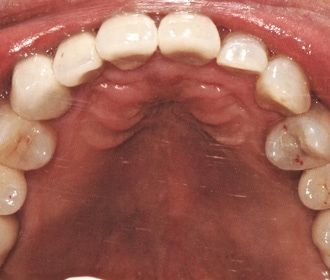

インプラント2次治療後、歯周組織移植などを行い、歯間乳頭が再生された。

-

アトランティスシステムにより、ジルコニアアバットメントがCAD/CAMにより作製された。

アトランティスのガイドにより正確に位置決め可能。 -

ジルコニアアバットメント上に装着されたプロビジョナル、矯正治療は継続。